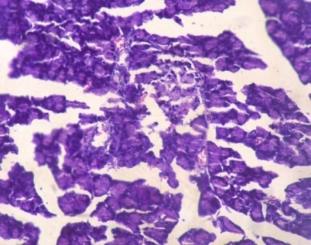

Effect of Hydroalcoholic extract of Linaria ramosissima (Wall.)Janch on pancreas by Histopathology

Fig 3A shows normal islets of langerhans and β cells in pancreas of normal control group.(non-diabetic) In positive control group

(Diabetic) the number of pancreatic islets as well as β-cells is reduced as compared to control group with most of β-cells being destroyed. (Fig 3B) Section of pancreas from groups treated with glibenclamide (Fig 3C) and both doses of test drug (Fig 3D & 3E) showed increase in pancreatic islets & number of β-cells in the pancreas. The damaged β-cell seen after induction of diabetes were no longer observed after treatment with extract. This indicates that the test drug causes regeneration of β-cell of islets of langerhans of pancreas and restores normal cellular appearance and size of islets with hyperplasia.

Fig. 3a: Normal Control (Non-diabetic)

Fig. 3b: Positive Control (Diabetic)

Fig. 3c: Glibenclamide Standred drug (10 mg/kg)

Fig. 3d: Test-1 (Low dose) 200 mg/kg

Fig. 3e: Test-2 (High dose) 400 mg/kg